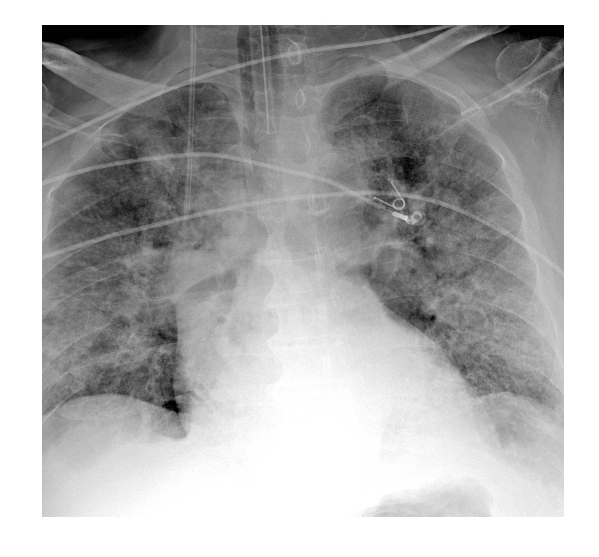

CXR of pulmonary TB?

* Upper lobes tend to be affected * irregular shadowing * cavitation * thick irregular walls